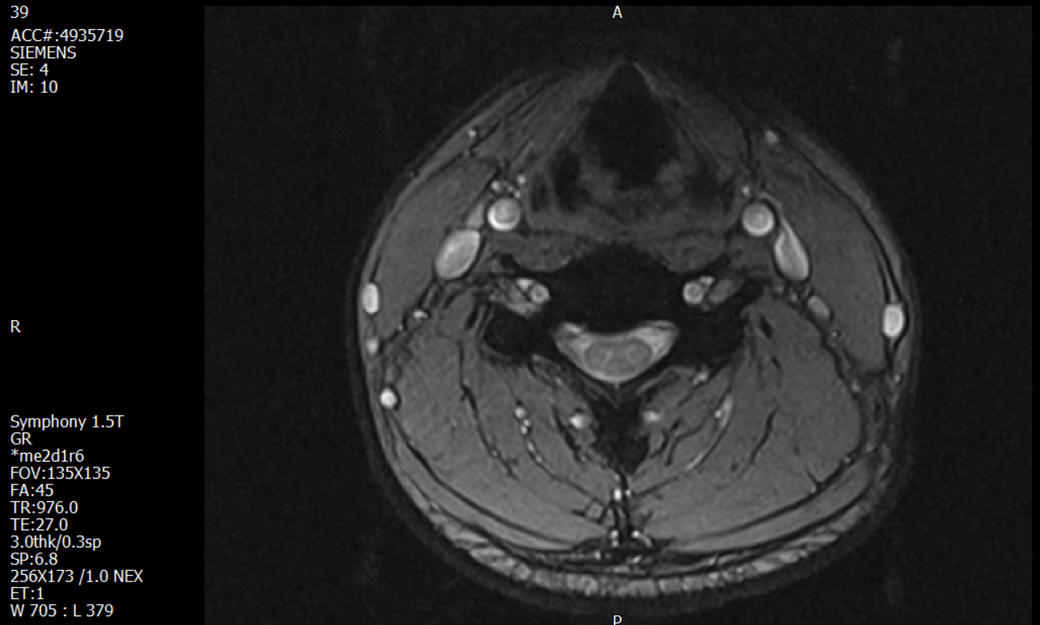

경추 요추 디스크 MRI판독 부탁드립니다.

- 3개월전 좌측 상지 저림(힘빠짐) 발생. 이틀뒤 에 좌측 하지 저림(힘빠짐) 발생.

(힘이 축처지는 느낌이라서 힘빠짐이라고 하지만, 실제 근력 문제, 감각이상, 활동 문제 없음)

-11월, 증상발생 직후 잠실소재 척추전문병원 MRI 요추경추 촬영 후 신경외과 박사 진료, 허리는 매우 건강, 경추는 퇴행성 진행되고 있지만 디스크라고 보기 어려움. 신경막만 살짝 건드리는 정도고 이 정도로 힘빠짐이나 저림이 오지 않고 원인은 다른 곳에 있을 가능성.

1. MRI 상 , 경추와 요추에 디스크가 있나요? 있다면 좌측 팔과 다리에 저림 및 힘빠짐을 줄 정도인가요?

• 1번 째 사진

• 1. MRI 사진을 보았을 때 디스크를 의심해볼 수 있는 소견이 살짝살짝 보이긴 합니다만, 상하지의 저림 및 힘빠짐을 유발할 정도인지는 솔직히 회의적입니다.

2. 영상의 퀄리티는 나쁘지 않아 보입니다. 굳이 재촬영을 하실 필요는 없어 보입니다.

3. 개인적으로는 디스크로 인한 증상이 아닐 것으로 보나, 만약 디스크가 맞다면 우연하게 목과 허리 디스크 발병이 이틀 간격을 두고 나타났을 가능성을 생각해야 하는데, 현실적으로 그 가능성이 높지 않습니다.

4. 말씀하신 것처럼 특히 요추부 MRI는 디스크를 찾기 어렵습니다.